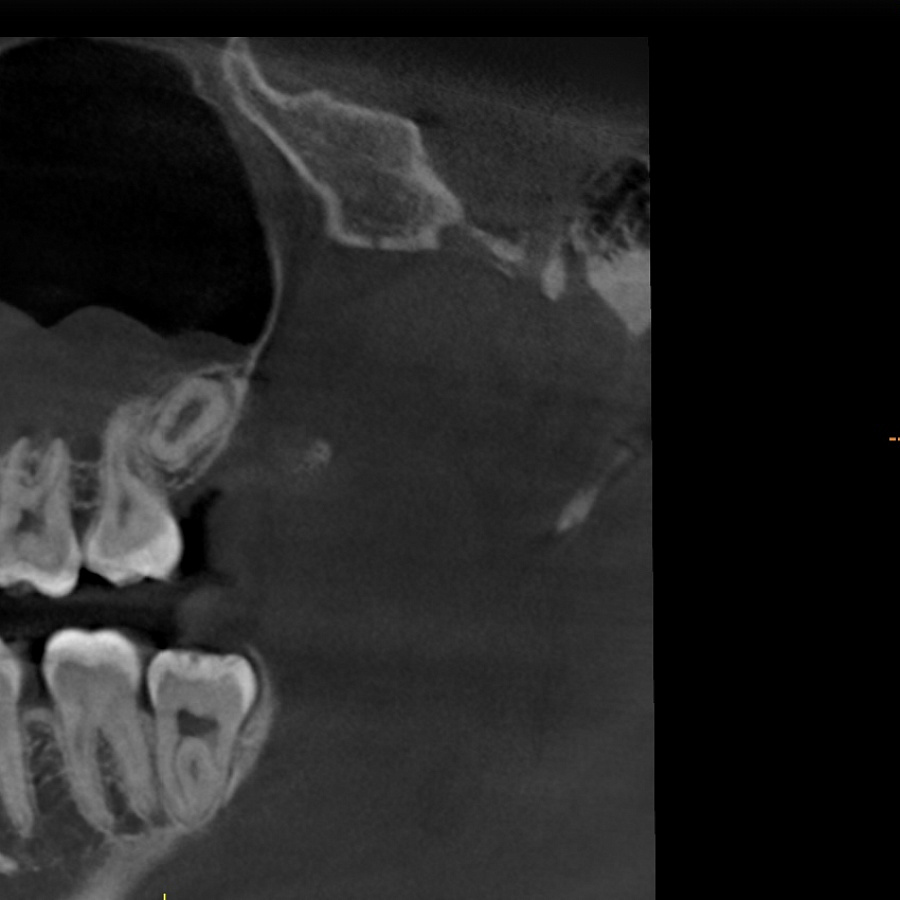

Зуб не прорезался, лежит горизонтально и направлен в сторону твёрдого нёба, мешает проведению ортодонтического лечения, выпрямлению зубных рядов. Около зуба проходит несколько важных анатомических структур, которые нельзя задеть, плюс зуб полностью погружён в костную ткань.